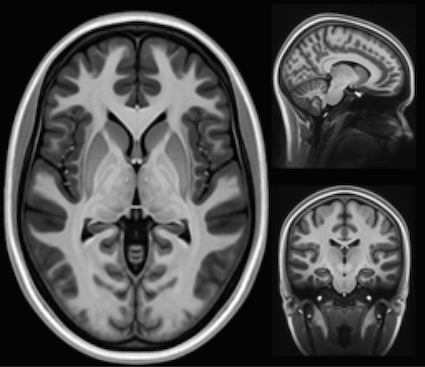

La maladie de Charcot, ou sclérose latérale amyotrophique (SLA), est une pathologie neurodégénérative qui détruit progressivement les neurones moteurs. Ce sont eux qui commandent les muscles. Quand ils meurent, le corps cesse d’obéir. Les muscles s’atrophient, la parole devient difficile, la déglutition se complique, puis la respiration elle-même finit par être atteinte. Le cerveau, lui, reste souvent intact. C’est ça qui rend la maladie particulièrement violente : lucidité totale dans un corps qui lâche.

D’abord, parce qu’on diagnostique mieux. Avant, beaucoup de patients étaient classés dans d’autres maladies neurologiques. Aujourd’hui, avec l’imagerie, les critères médicaux plus précis et la vigilance accrue, on identifie davantage de cas. Donc mécaniquement, les chiffres montent.